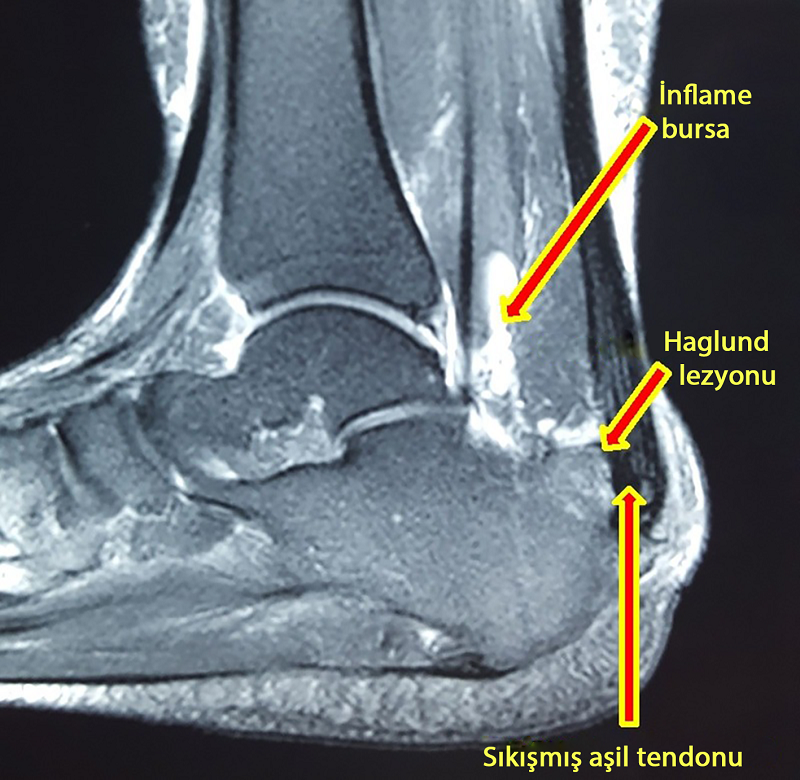

Haglund hastalığının teşhis edilmesi zor olabilir, çünkü semptomlar Aşil tendiniti de dahil olmak üzere diğer ayak sorunlarıyla ilişkili semptomlara benzer. Kemik büyümesinin tam olarak görmek ve ayakta veya ayak bileğinde soruna neden olan başka bir şeyin olup olmadığını görmek için röntgene çekilir.

Aynı hastanın MR görüntüsü.